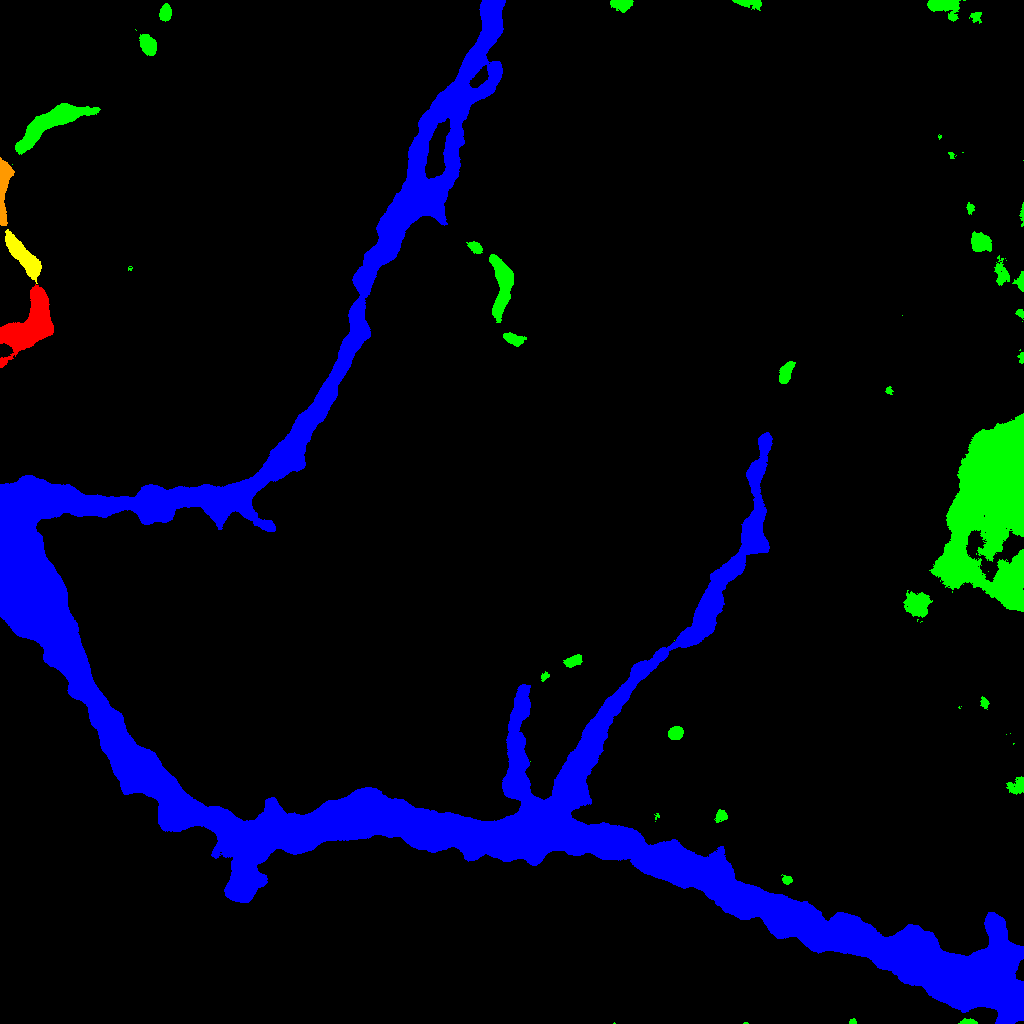

Otro problema considerado consiste en contar el número total de neuronas que aparecen en una imagen de cultivo (véase la figura 2). Para ello hay que localizar los núcleos de neuronas que aparecen en la imagen y diferenciarlos de otros elementos (como astrocitos, células que no son neuronas). Este recuento es necesario para el estudio de la muerte neuronal que se produce, por ejemplo, al sufrir un ictus. En este estudio se compara el número de núcleos disponibles antes y después de la aplicación de una sustancia a la muestra. Las imágenes consideradas en este problema tienen un tamaño de 16193×10279161931027916193\times 10279 píxeles, lo que en este caso equivale a 3676×2333367623333676\times 2333 micras, y se obtienen como un mosaico de 8×5858\times 5 imágenes de tamaño 2048×2048204820482048\times 2048 píxeles (con un solapamiento del 2%percent22\leavevmode\,\%{}).

Refer to caption

Figura 2: Estudio de la muerte neuronal

La idea de conexión aparece también en el problema del cálculo del número de núcleos (o neuronas) en imágenes de inmunoflorescencia. En este caso, se parte de una imagen en dos canales (correspondientes a núcleos celulares y neuronas), y a partir de las componentes conexas obtenidas en la intersección se aplican diversos criterios geométricos para seleccionar las que corresponden a núcleos de neuronas (y desechar, por ejemplo, las que corresponden a núcleos de astrocitos u otro tipo de células del sistema nervioso que no interesa considerar). Una vez realizada la selección, el número total de componentes conexas nos determina el número de neuronas disponibles en la imagen estudiada. Entre los criterios geométricos utilizados para la selección, se considera la forma de las componentes conexas (eliminando las que son oblongas, esto es, que la diferencia de tamaño entre el eje mayor y el eje menor sea mayor que 2) y el tamaño (se desechan las de más 200 píxeles, que suelen corresponder a astrocitos o clústeres de núcleos, y las de menos de 40 píxeles, que se consideran ruido). También se eliminan aquellas componentes que se encuentran en una zona muy densa. Para ello se realizan diferentes círculos concéntricos alrededor de la misma comprobando si la moda va disminuyendo; si no decrece, el posible núcleo se desecha por corresponder a una nube de núcleos (o también un clúster).

Para el recuento y la localización de núcleos de neuronas en una imagen de cultivo se ha creado un plugin para Fiji llamado NucleusJ [15]. En este caso, el programa parte de una imagen en dos canales que corresponden a núcleos y neuronas. En primer lugar se les aplica a ambas imágenes diferentes filtros para hacer más acertada su binarización. Tras ello se cuenta el número total de componentes conexas que aparecen en la imagen de los núcleos (número total de núcleos, ya sean de neuronas o de otras células). Después se solapan las dos imágenes y se seleccionan aquellos núcleos en los que hay intersección con la imagen de las neuronas. El programa permite especificar algunos parámetros, como el tamaño mínimo y máximo para los núcleos considerados o la diferencia máxima entre el eje mayor y el eje menor, descartando automáticamente los que no cumplen las condiciones deseadas. El plugin devuelve una imagen con los núcleos seleccionados como se muestra en la figura 10, siendo posible modificar los parámetros y el umbral para ajustar el resultado. También se permite seleccionar manualmente más núcleos o descartar algunos de los propuestos. Finalmente, el programa informa del número total de neuronas y el número total de células obtenidos.

Figura 10: Resultado de NucleusJ